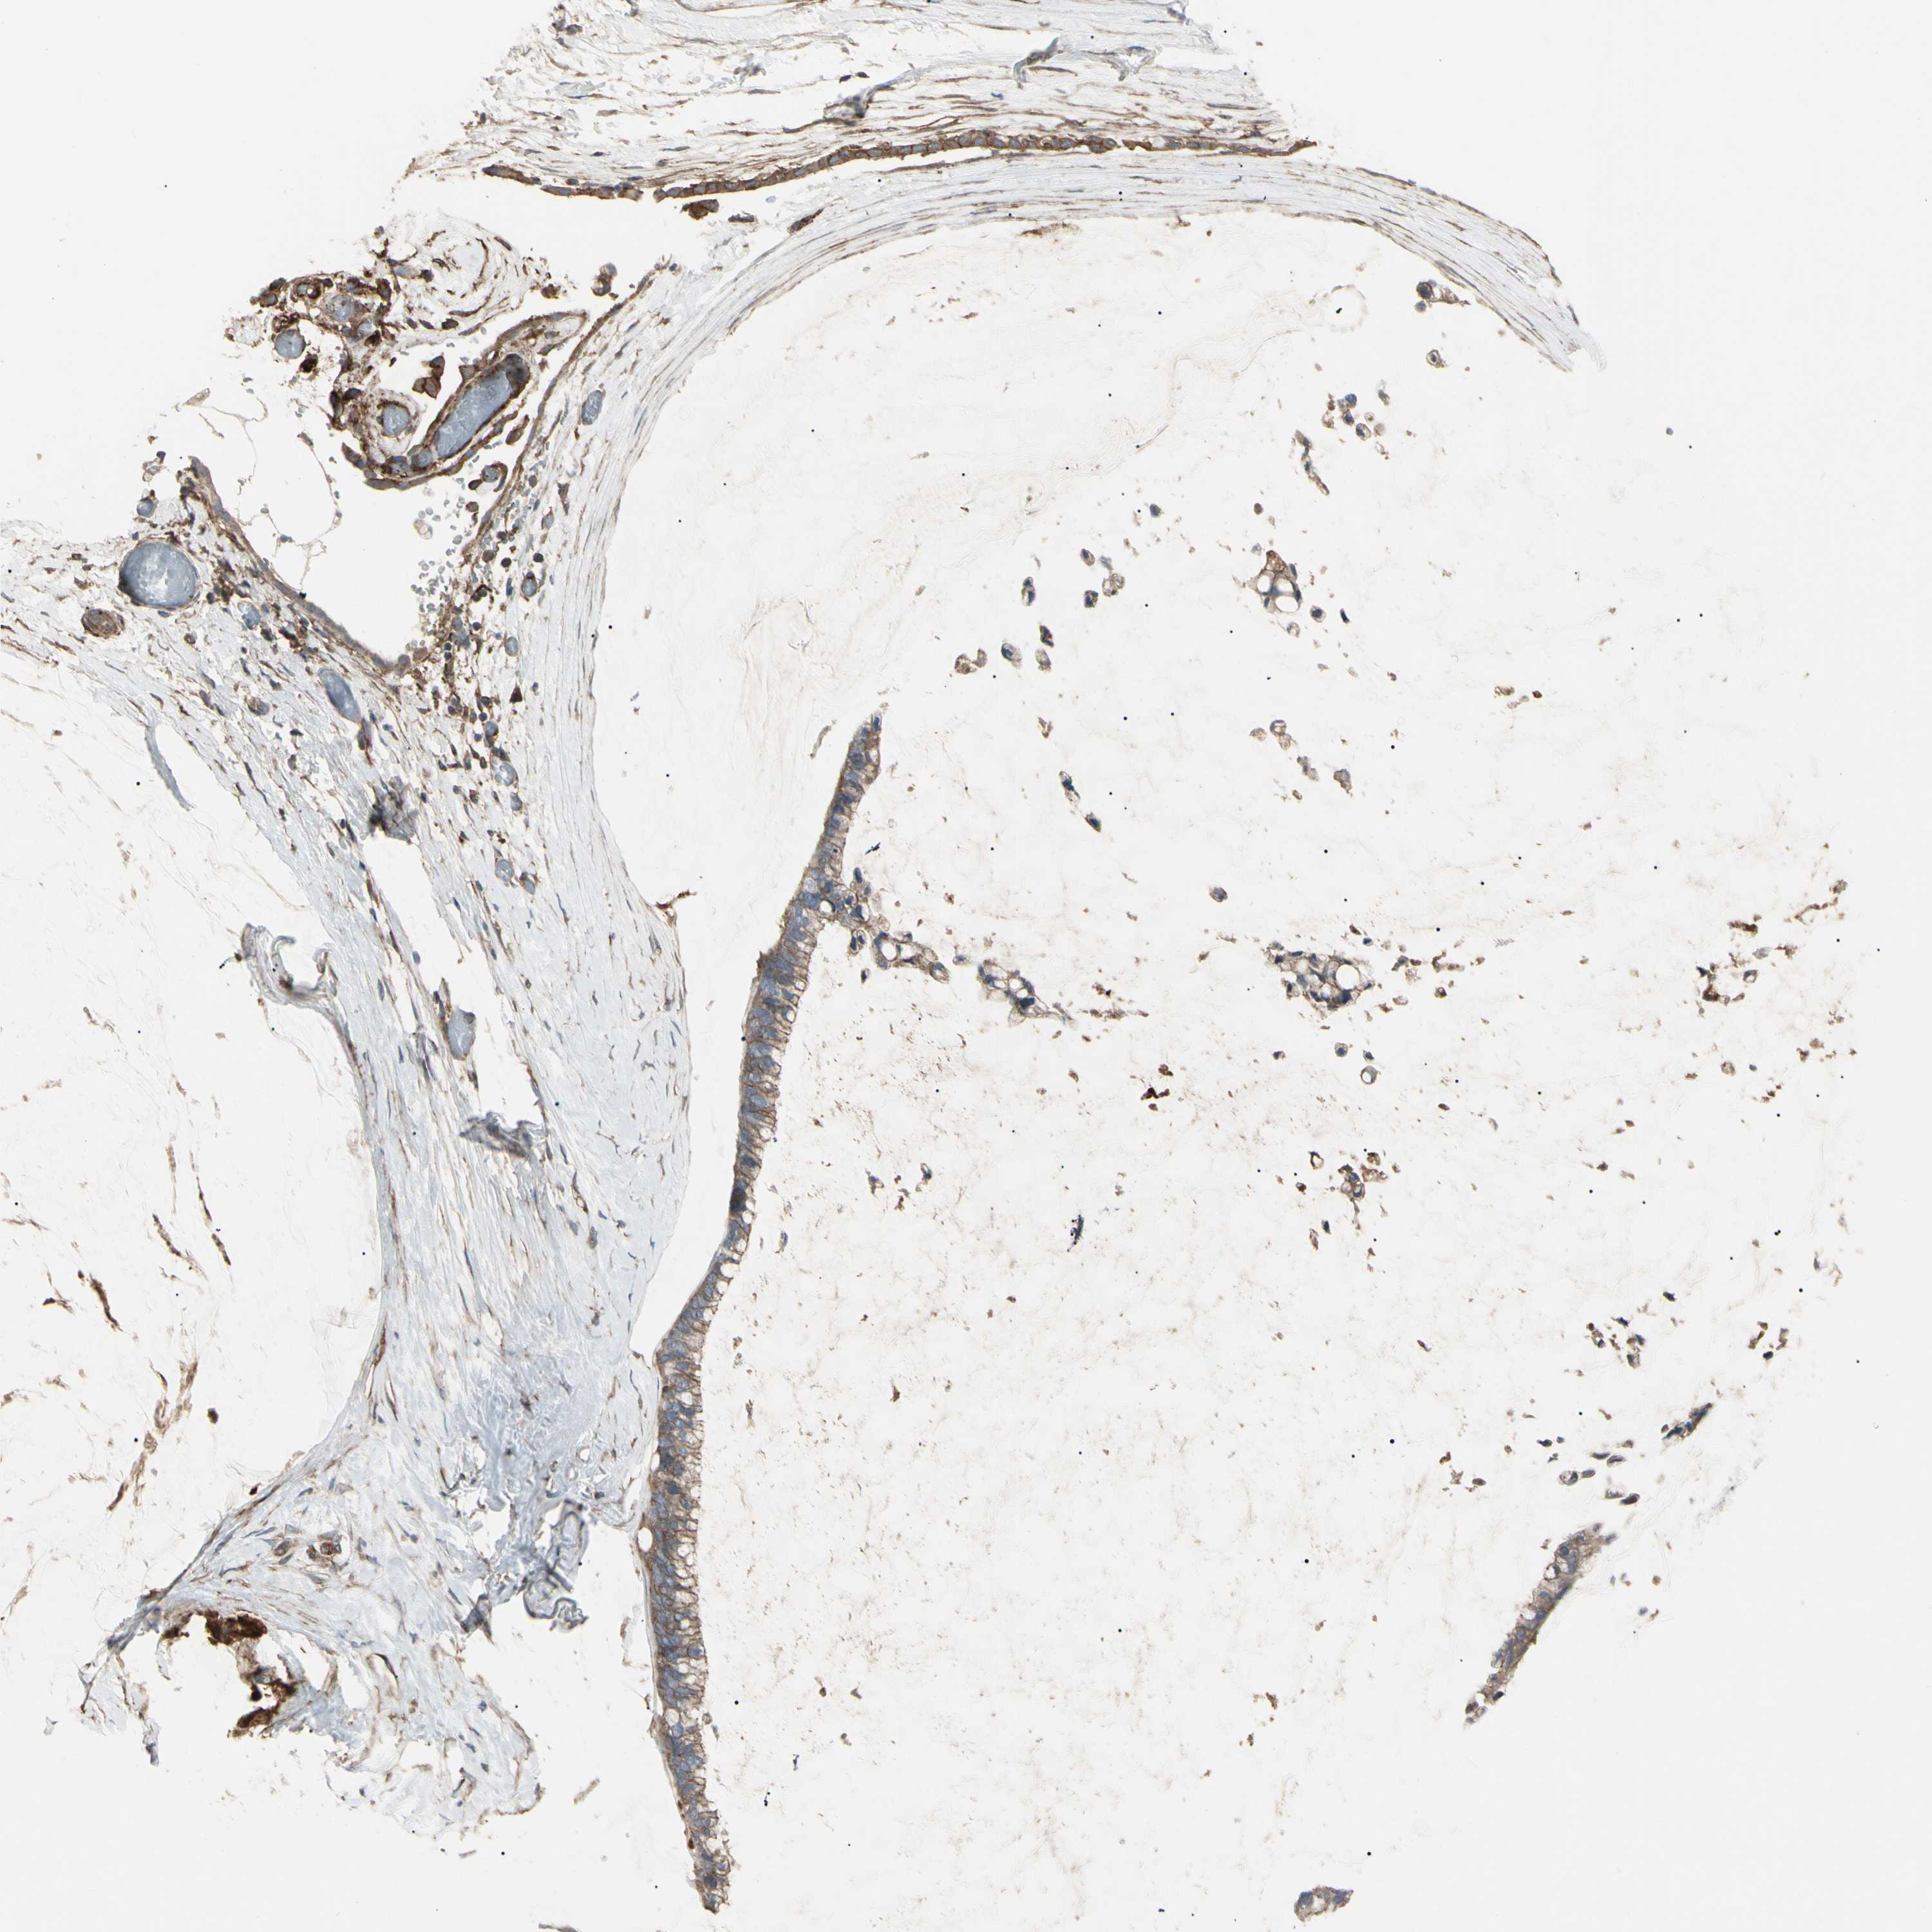

OVARIAN CANCER - Protein expressioni

A mouse-over function shows sample information and annotation data. Click on an image to view it in a full screen mode. Samples can be filtered based on level of antibody staining by selecting one or several of the following categories: high, medium, low and not detected. The assay and annotation is described here.

Note that samples used for immunohistochemistry by the Human Protein Atlas do not correspond to samples in the TCGA dataset.

Antibody stainingi

Antibody staining in the annotated cell types in the current human tissue is reported as not detected, low, medium, or high, based on conventional immunohistochemistry profiling in selected tissues. This score is based on the combination of the staining intensity and fraction of stained cells.

Each image is clickable and will lead to virtual microscopy that enables deeper exploration of all samples and also displays staining intensity scores, fraction scores and subcellular localization as well as patient and tissue information for each sample.

Antibody HPA009285

Antibody HPA017139

Antibody CAB017826

Cystadenocarcinoma, serous, NOS

Carcinoma, endometroid

Cystadenocarcinoma, mucinous, NOS

Carcinoma, NOS